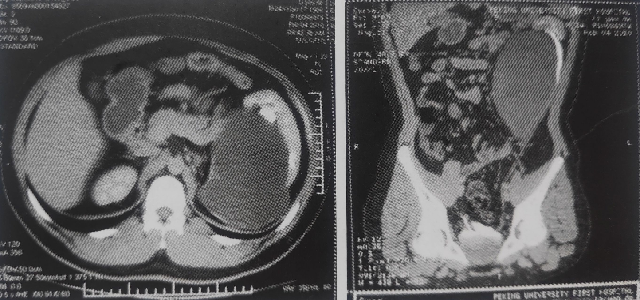

这是一个左肾的重复肾畸形合并左上肾积水.

图片尺寸640x300